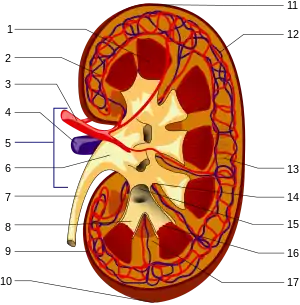

1. Renal pyramid • 2. Interlobular artery • 3. Renal artery • 4. Renal vein 5. Renal hilum • 6. Renal pelvis • 7. Ureter • 8. Minor calyx • 9. Renal capsule • 10. Inferior renal capsule • 11. Superior renal capsule • 12. Interlobular vein • 13. Nephron • 14. Renal sinus • 15. Major calyx • 16. Renal papilla • 17. Renal column | |